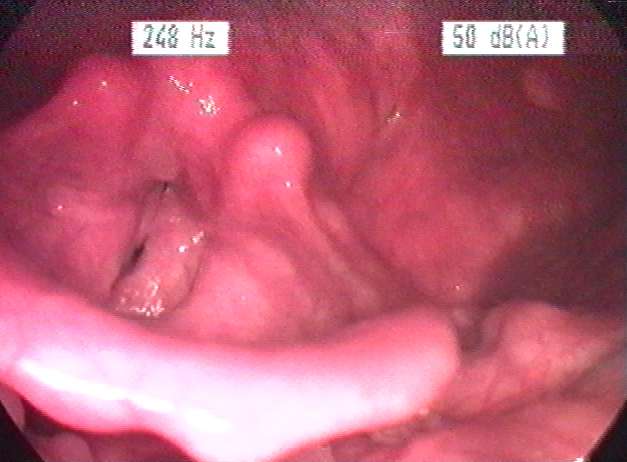

후두염은 후두의 염증을 의미합니다. 후두염은 대개 바이러스나 박테리아가 원인이 되어 발생하며, 연기나 화학 물질 등으로 인해서도 발생할 수 있습니다.

바이러스 감염은 급성 후두염의 가장 흔한 원인입니다. 라이노바이러스(감기), 인플루엔자, 호흡기세포융합바이러스(RSV)와 같은 일반적인 바이러스는 성대와 주변 조직에 염증을 일으킬 수 있습니다. 감염되면 성대가 붓고 성대 진동과 음성 생성에 영향을 미칩니다. - 박테리아 감염

소리를 지르거나 비명을 지르거나 장시간 큰 소리로 말하는 등 과도하거나 부적절한 음성 사용은 성대에 무리를 주어 후두 염증을 유발할 수 있습니다. 이러한 형태의 후두염은 종종 “성대 남용” 또는 “가수 결절”이라고 불립니다. - 위식도 역류 질환(GERD)

후두염증상

- 쉰 목소리

쉰 목소리는 대표적인 후두염증상입니다. 쉰 목소리는 거칠고 숨이 차거나 긴장된 목소리로 나타납니다. 성대에 염증이 생기면 음정과 말의 질에 변화가 생깁니다. - 음성 손실